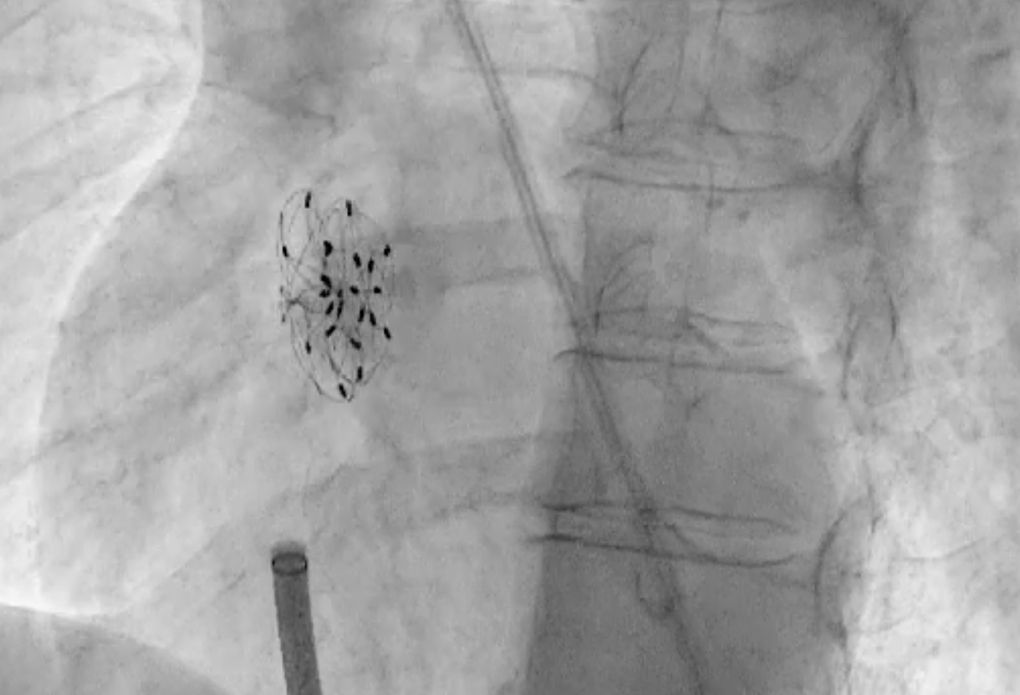

Katheterinterventionell können wir PFOs und ASDs mittels Schirmchen-Okkludern schnell und sicher verschließen.